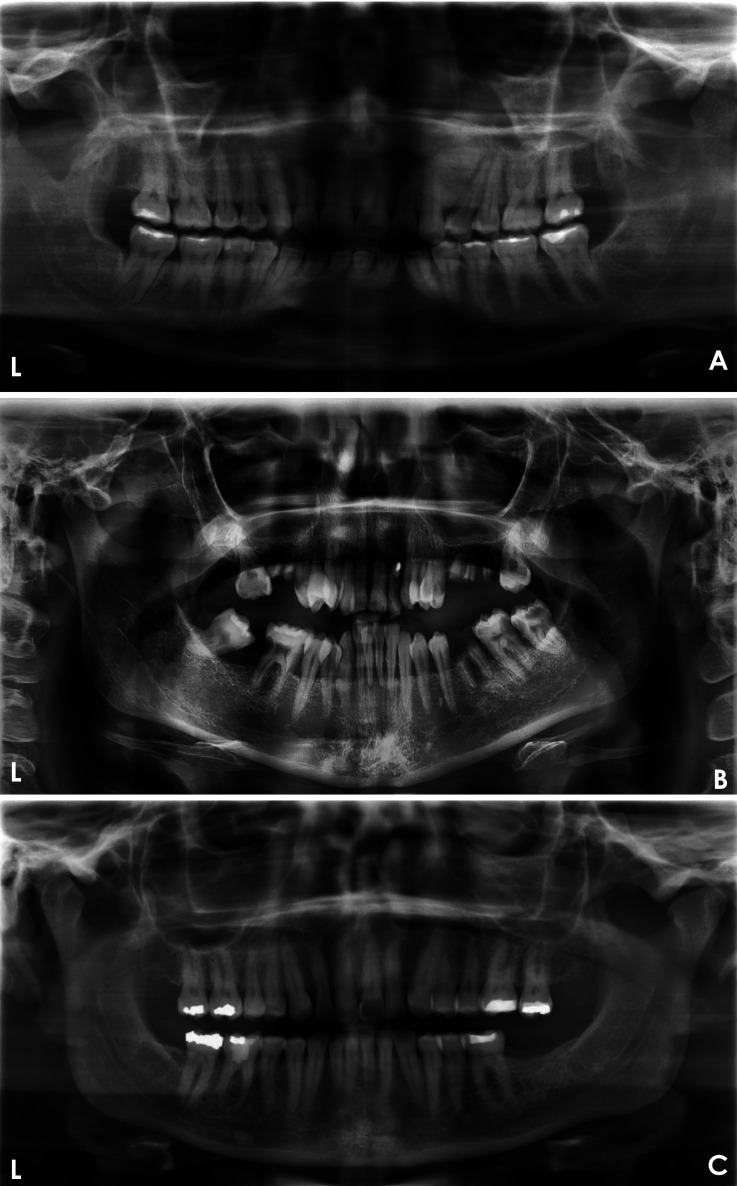

Materials and methods: This study aimed to develop a deep learning (DL)-based model for evaluating the quality of dental panoramic radiographs. A dataset of 1,000 panoramic images, collected from 2018 to 2023, was assessed by 2 trained dentists using predefined grading criteria for contrast/density, artifact presence, coverage area, patient positioning, and overall quality. These expert-annotated scores were used as the ground truth to train and validate 5 YOLOv8 classification models, each targeting a specific quality criterion. The models' performance was evaluated on a separate test set using performance metrics.